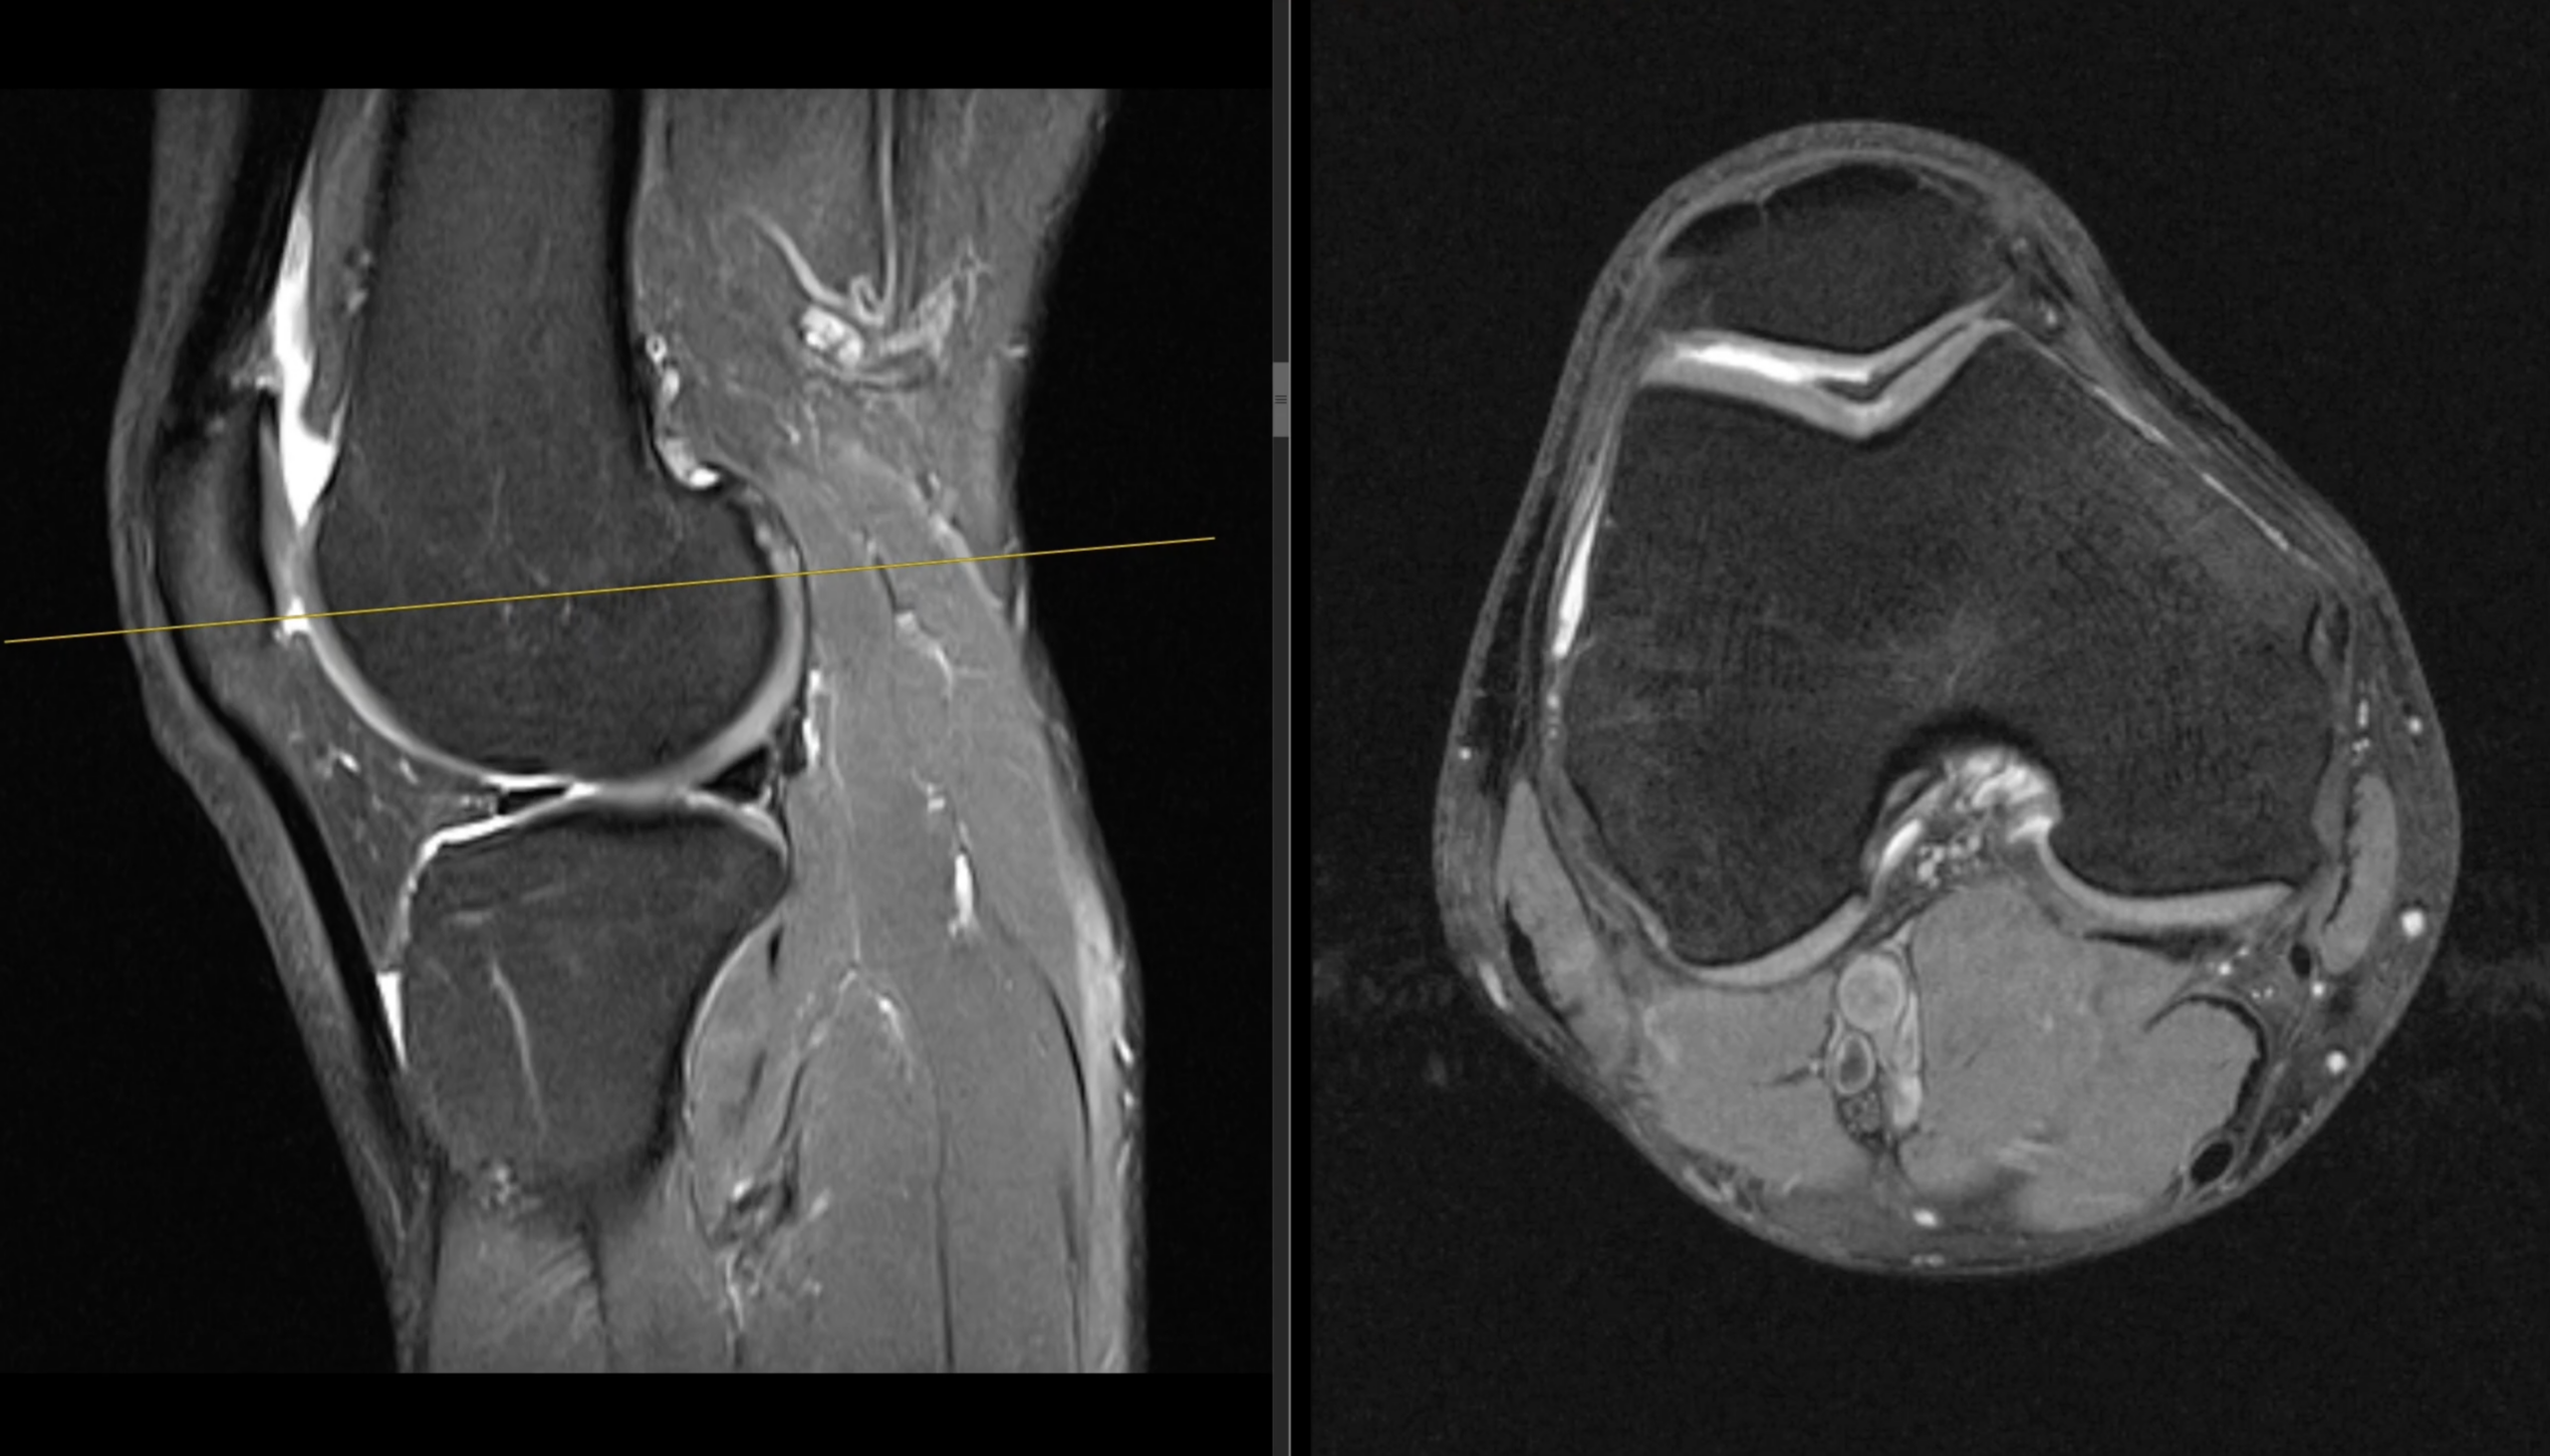

„Knie – verschiedene Phasen / Befunde“

Mittlerweile ging man von einem Knorpelschaden aus. Dieser lag mittig genau unter der Patellarsehne. Darum wurde wohl auch in den Jahren zuvor eine andere Diagnose gestellt und dementsprechend behandelt. So what.

Knorpelschaden am Knie. Eine alte Geschichte, die mich 2016 schon einmal am rechten Knie begrüßte. Damals sagte man mir schon, ich soll das Laufen sein lassen. Damals lief ich durch den Knieschmerz und er verschwand. Nun ist es am selben Kniegelenk mittig. Grad 2–3.

Diese Einteilung in Schweregrade ist meiner Erfahrung nach mit Vorsicht zu genießen. Oft wird das nach der Größe des Defektes eingeteilt. Im Endeffekt ist für mich das Gefühl ausschlaggebend.

Als Methode wurde bei mir eine Mikrofrakturierung durchgeführt. Der defekte Knorpel wurde entfernt. Der Knochen darunter angebohrt. Aus diesem Loch soll Knochenmark herausbluten und eine Art Ersatzknorpel bilden.